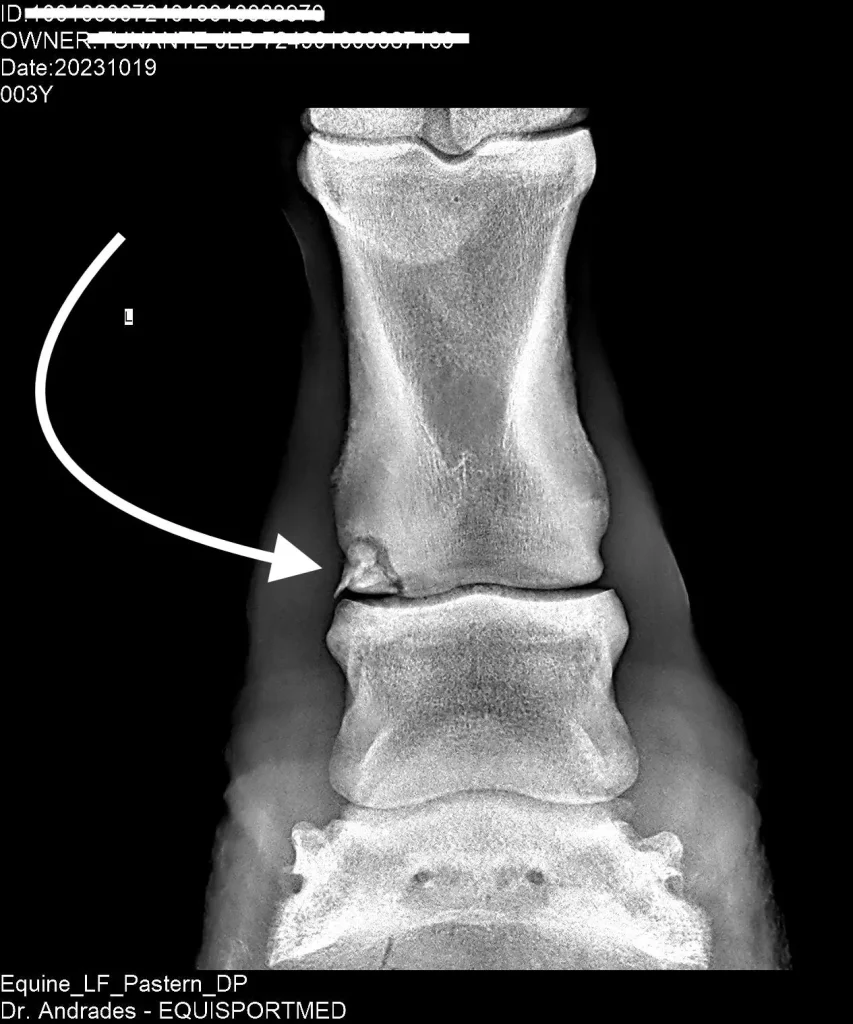

Advanced Diagnostic Imaging

We carry out diagnostic tests such as scintigraphy, magnetic resonance imaging, among others, in collaboration with equine veterinary hospitals.